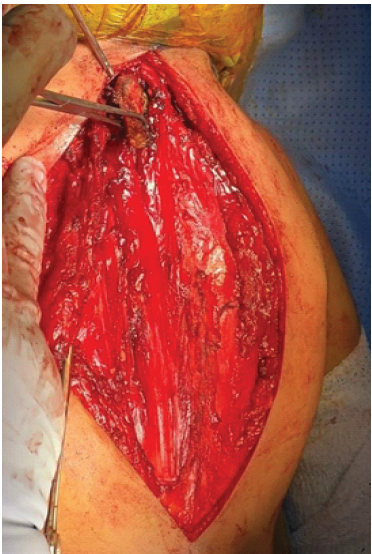

The patient underwent bilateral Modified Woodward’s procedure under general anesthesia. She was placed in the prone position, and the surgical field was prepared in a sterile fashion with exposure of the posterior neck, back, and scapulae. A midline posterior incision was made extending from C2 to T12. Dissection was carried out through the posterior scapular line to access the left scapula. The periscapular muscles were reflected, and the cartilaginous portions of the scapula were resected (Fig. 1). Omovertebral bar was identified and resected (Fig. 2).

Figure 1: The omovertebral bar with the cartilaginous connection to the scapula (forceps holding cartilaginous part).